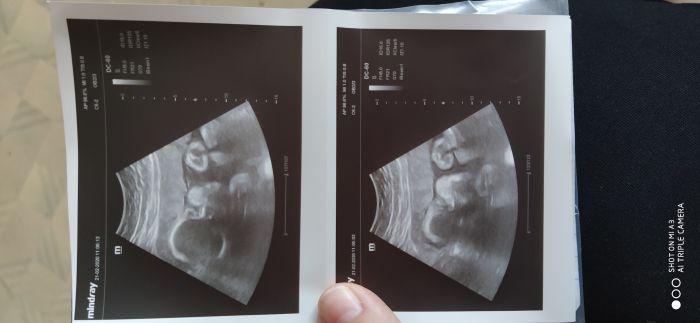

To jsem ještě jednou já ... Jsem neskutečně šťastná ... Dnes nám vyšly nádherné UZV fotky, kde je krásně naše princezna vidět :) máme 1663 g a jsme o týden větší tedy. Nicméně jsem se s vámi musela o to podělit. Jsem fakt happy z toho :)

[1137450] děkuji, Irčo :) prostě úplně v té dolní fotce vidím očka, nosanek, prostě jako by to bylo 3 D :) možná blaznim, ale jsem šťastná :)